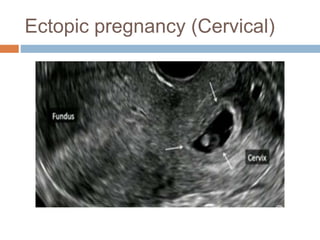

Ectopic pregnancy (Cervical)

Ectopic pregnancy